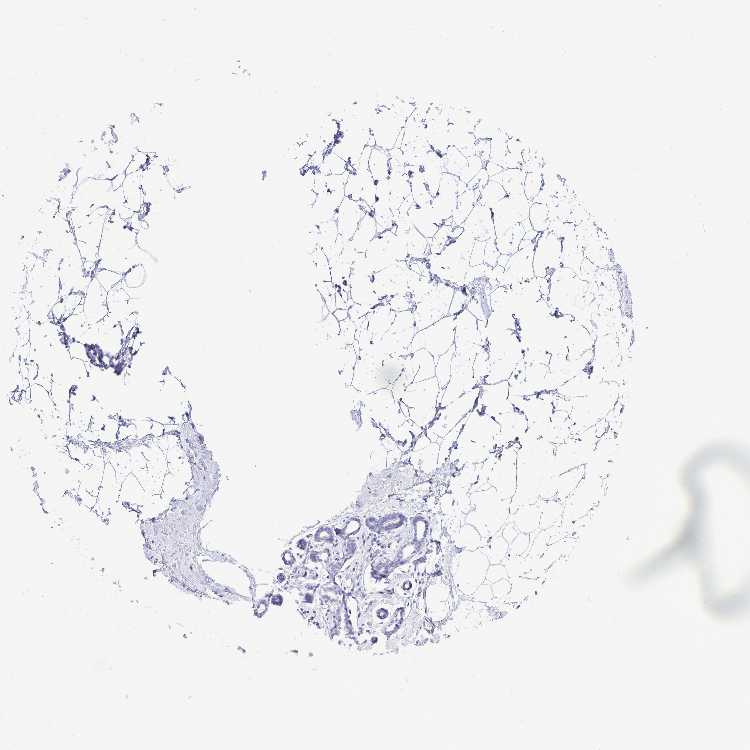

BREAST - Antibody stainingi

Antibody staining in the annotated cell types in the current human tissue is reported as not detected, low, medium, or high, based on conventional immunohistochemistry profiling in selected tissues. This score is based on the combination of the staining intensity and fraction of stained cells.

Each image is clickable and will lead to virtual microscopy that enables deeper exploration of all samples and also displays staining intensity scores, fraction scores and subcellular localization as well as patient and tissue information for each sample.

Antibody HPA054719

Adipocytes Not detected

Glandular cells Not detected

Myoepithelial cells Not detected